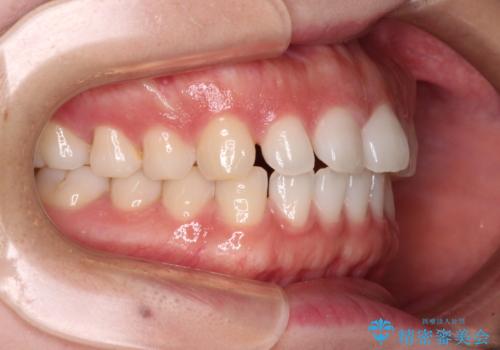

すきっ歯とオープンバイト インビザライン・ライトで改善

オープンバイトのため、奥歯に負担のかかる咬合状態であったので、矯正治療を提案したところ、希望をされました。

すきっ歯程度の軽度の歯列不正であったため、インビザライン・ライトにより咬合改善を行うこととしました。

オープンバイトやすきっ歯は、舌突出癖によりあっという間に後戻りをするため、矯正治療前からトレーニングを行っていただき、更には後戻り防止のワイヤーリテーナーを併用しています。